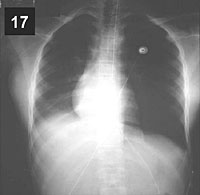

ESQUEMA 17 Comentario placa 17 Detrás del corazón se distingue una sombra triangular paravertebral que corresponde al lóbulo inferior derecho colapsado. Aunque no se viera esta imagen directa del lóbulo retraído, la existencia de la atelectasia sería detectable por el desplazamiento del corazón hacia la derecha y el ascenso diafragmático. Pase a la placa 18 que corresponde al mismo paciente unas pocas horas después de haberse aspirado broncoscópicamente un gran tapón mucoso que ocluía el bronquio del lóbulo inferior derecho. Observe la desaparición de la condensación retrocardíaca y la corrección de los desplazamientos del diafragma y mediastino. |